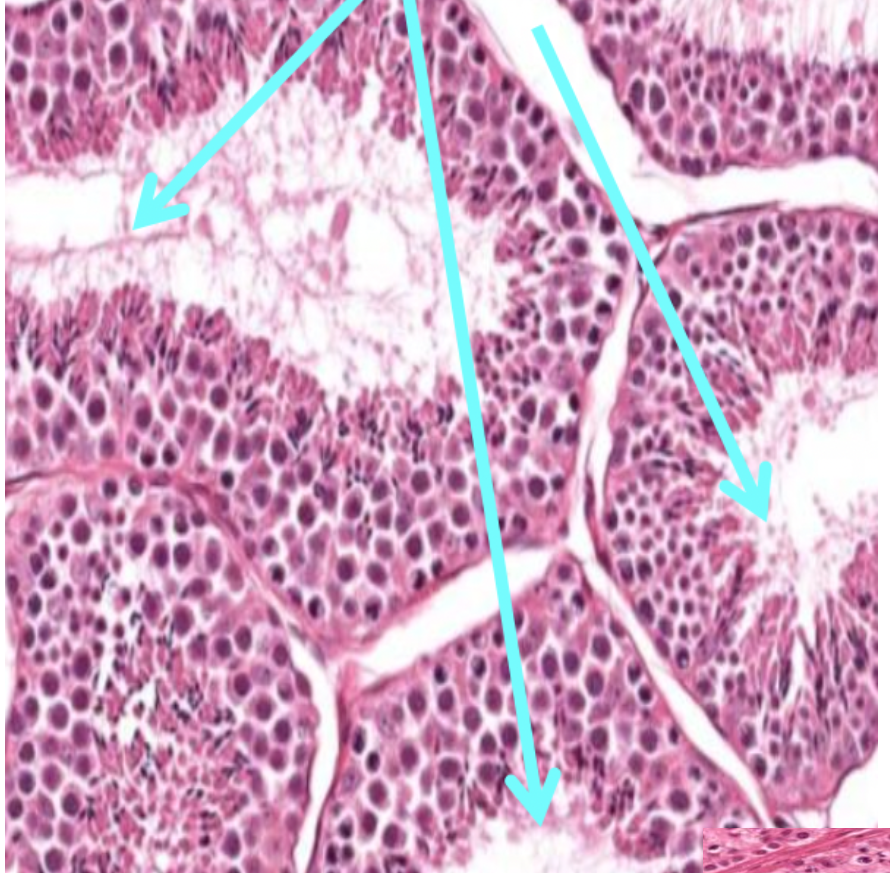

Whar is SPERMATOGONIA?

Spermatogonia are the primitive germ cells found in the seminiferous tubules of the testes

They are the earliest stage of male germ cells and serve as the stem cells for sperm production (spermatogenesis)

What does the arrows in this image show?

Semoniferous Tubules

What kind of cell is the pink ones shown in this image?

Sertoli cells